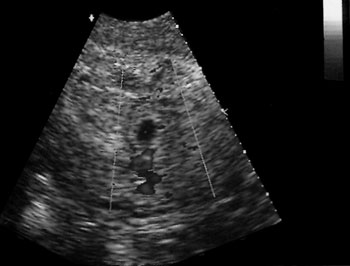

Εικόνα 1. Διακοιλιακός υπερηχογραφικός

έλεγχος έκτοπης κύησης.

Το διακολπικό υπερηχογράφημα είναι ευρέως αποδεκτό ως η καλύτερη επιλογή, έναντι

του διακοιλιακού στη διάγνωση της έκτοπης κύησης.(11) Το διακοιλιακό υπερηχογράφημα

δεν είναι πρακτικό, εξαιτίας της καθυστέρησης πλήρωσης της κύστης και της μη

ικανοποιητικής ποιότητας της εικόνας, ειδικά σε παχύσαρκες γυναίκες. Μερικοί

έχουν καταλήξει ότι η χρήση μόνο του διακολπικού υπερηχογραφήματος αποτελεί

μια πλήρη εξέταση για έκτοπη κύηση, παρόλο που άλλοι έχουν προτείνει τη χρήση

και των δύο τεχνικών με στόχο την αλληλοσυμπλήρωσή τους, καθώς ο διακοιλιακός

υπερηχογραφικός έλεγχος προσδιορίζει μάζες που βρίσκονται ψηλά στην πυελική

κοιλότητα, έξω από την εμβέλεια της ενδοκολπικής κεφαλής.(8-11) Επίσης, το διακολπικό

Οι εξαρτηματικές μάζες απεικονίζονται καλύτερα με το διακολπικό υπερηχογράφημα

σε σύγκριση με το διακοιλιακό, οδηγώντας στο συμπέρασμα ότι το διακολπικό υπερηχογράφημα

παρουσιάζει μεγαλύτερη ευαισθησία εντόπισης άμεσων σημείων στην έκτοπη κύηση

(εικόνες 1, 2). Επιπλέον, ακόμη και όταν η διαγνωστική ευαισθησία του διακολπικού